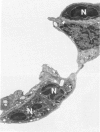

The morphogenesis of pulmonary lesions and associated edema induced by the pulmonary toxicant 3-methylindole (3-MI) was studied by combined light and transmission electron microscopy. Weanling male CD-1 mice received 3-MI dissolved in corn oil by intraperitoneal injection and were studied at intervals from 2 to 360 hours after treatment. Interstitial edema was observed as early as 2 hours and was associated with focal cytoplasmic swelling and membrane alterations in both capillary endothelial cells and Type I alveolar epithelial cells and with sequestration of neutrophils. Cell swelling, cytoplasmic fragmentation, and necrosis of Type I epithelial cells was most severe at 24-48 hours after treatment. Multifocal hypertrophy and hyperplasia of Type II alveolar epithelial cells was observed at 24-96 hours after treatment. Platelet aggregation and aggregates of fibrin were frequently observed in capillaries and small arteries and veins as early as 4 hours and as late as 48 hours after treatment. In airways, the nonciliated bronchiolar epithelial (Clara) cell was the predominant cell affected. Initial lesions in nonciliated cells consisted of loss of microvilli and secretory granules followed by marked swelling of the endoplasmic reticulum and mitochondria. Necrosis of cells lining airways was most pronounced at 24-48 hours after treatment. By 144 hours after administration, pulmonary repair was complete. It is concluded that the mouse is a useful model of 3-MI-induced pulmonary injury and that damage to both Type I alveolar epithelial cells and capillary endothelial cells is important in the pathogenesis of 3-MI-induced pulmonary edema.